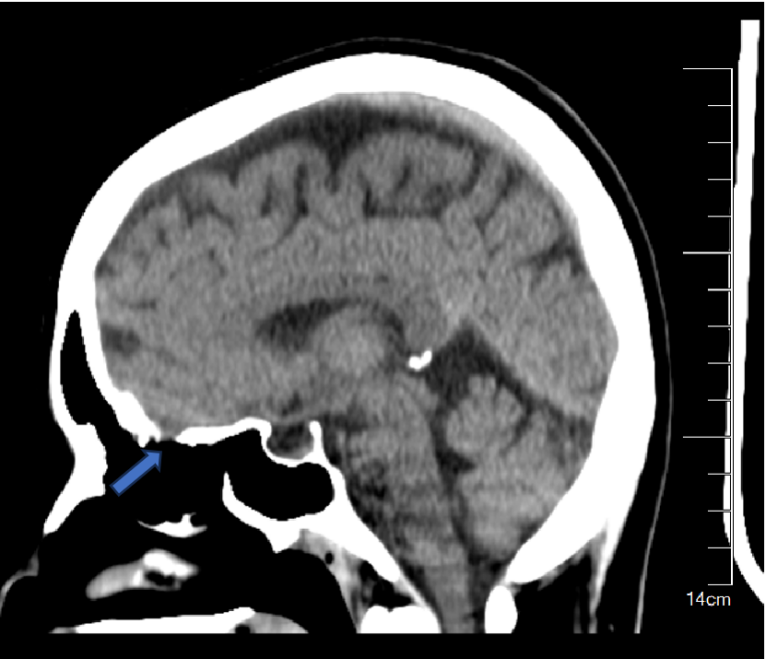

蓝色箭头所在位置就是脑脊液漏出之处

幸运的是,张女士在术前通过相关检查找到了漏口的位置。